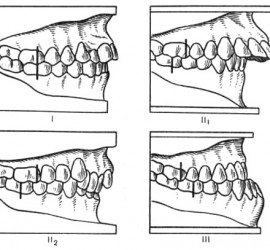

Опорными частями являются кламмеры или замковые соединения, телом — седловидный базис с искусственными зубами. Жевательное давление, падающее на тело съемного мостовидного протеза, передается так же, как и в несъемном, на опорные зубы. Ткани, лежащие под телом протеза, не испытывают непосредственно жевательного давления. Большим преимуществом съемных мостовидных протезов является то, что одним протезом можно соединить различные группы зубов, например, жевательные с обеих сторон или фронтальные и жевательные. Соединение зубов правой и левой сторон челюсти или зубов, различно функционально ориентированных в одну систему, позволяет укрепить зубы с пораженным пародонтом. Кроме того, расширяются возможности применения мостовидных протезов.